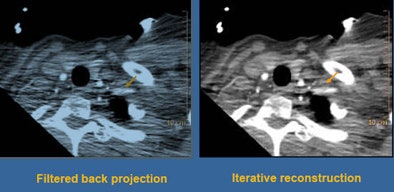

![]() |

| Photon starvation in the shoulder region was even more pronounced when the mAs and kV were reduced in the second study; fortunately, iterative reconstruction brought out a large amount of image detail. |

Using iterative reconstruction, "we cleaned things up a little bit through the body," Halliburton said. "What's impressive is the way we were able to clean things up through the shoulders. I think the use of iterative reconstruction for these really low-dose techniques is enabling us to deal with the shoulder issue."